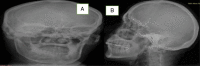

Case presentation: High-grade MEC of the lacrimal gland of the right eye was diagnosed in an orbital exenteration specimen of a 60-year-old HIV-positive man. He presented to the eye unit of a mission hospital in Jos, Nigeria with significant visual impairment in the right eye and a rapidly growing painful superolateral orbital mass. The tumour invaded and completely obliterated the anterior chamber. The lens, ciliary body, and iris were displaced posteriorly but were free from tumour infiltration. The tumour was exenterated, and the patient was subsequently referred for adjuvant radiotherapy. No evidence of recurrence or metastasis has been noted 15 months post-surgery.